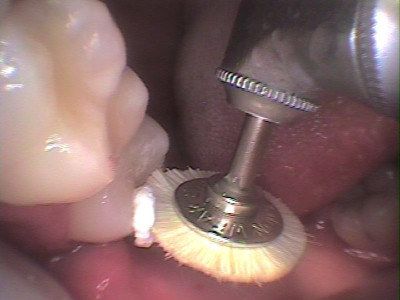

Anatomía y pulido final